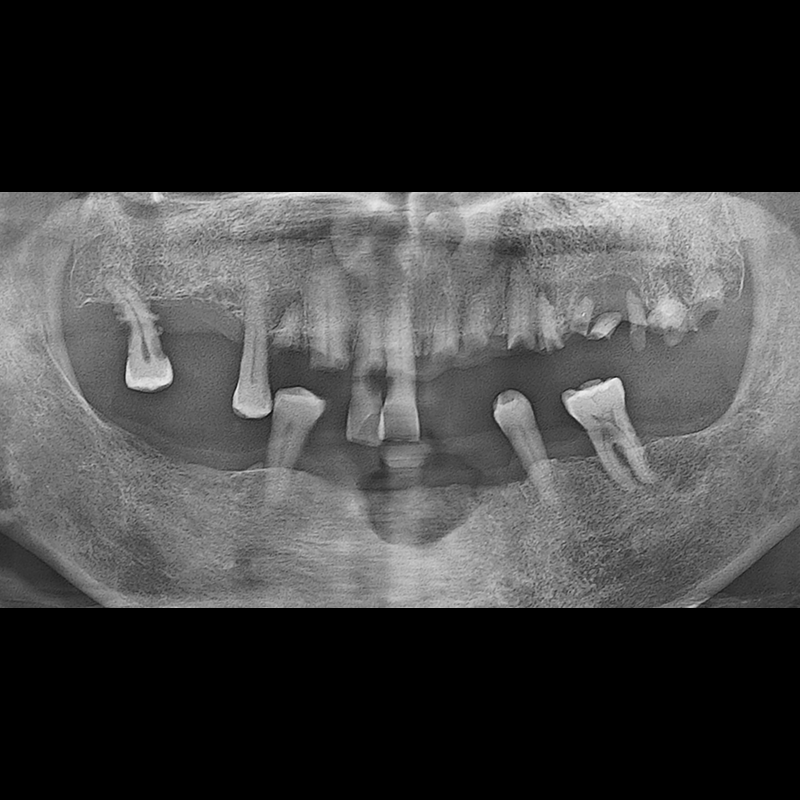

BEFORE AFTER

임플란트 전후사진 2025.05.30

결손된 치아 부분과 살리기 힘든 치아 위치에 임플란트를 식립하였습니다.